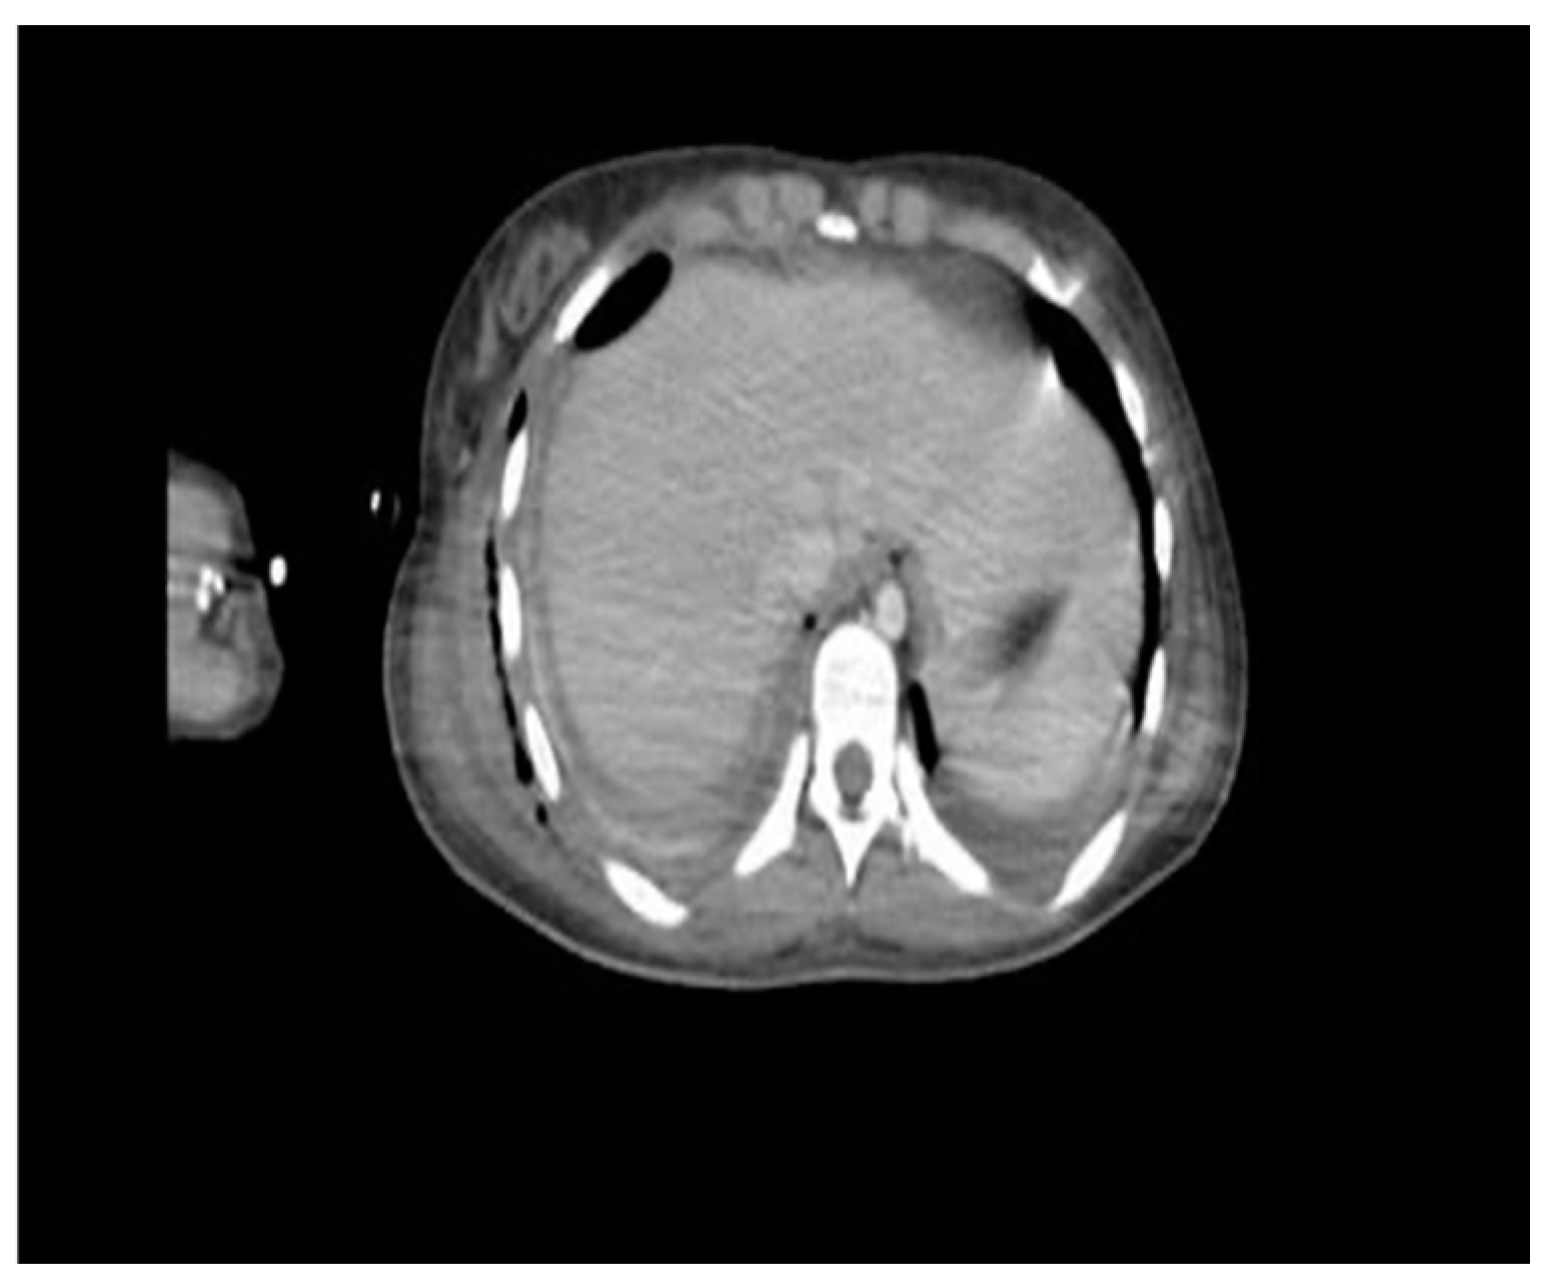

On the other hand, the computed tomography (CT) scan showed a loculated fluid collection on the entire right lung parenchyma, pneumothorax of the right upper lobe, and thickening of the right sternocleidomastoid muscle (Figure 2).

Figure 2. Contrasted computed tomography. Abscessified collection with hydroaeric levels, atelectasis of the parenchyma, lower zone consolidation, loculation in the base, and occlusion of the pleurostomy.